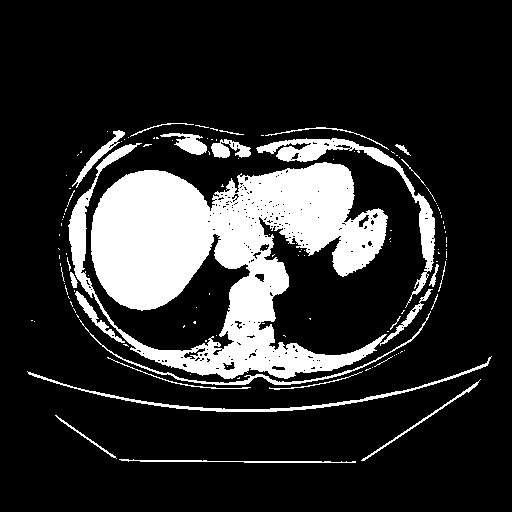

Original NATIVE CT scan (input)

Full window (WL 1023.5, WW 4095 β†’ Low βˆ’1024, High +3071)

Actual HU range: [-1024.0, 3071.0]